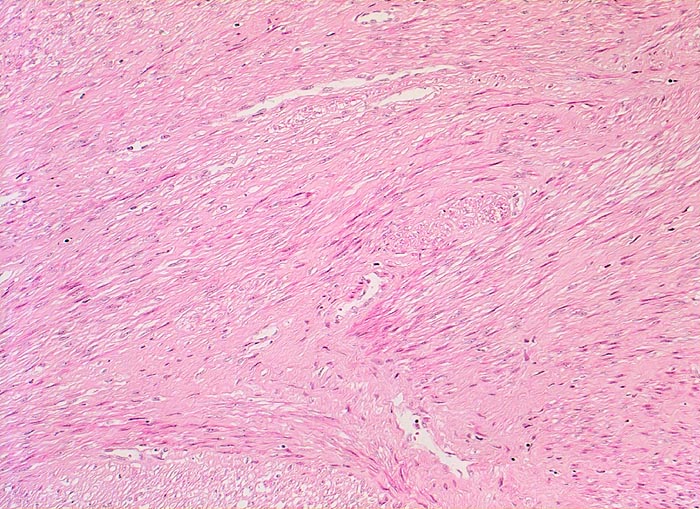

Fibroleiomyom

benigner Tumor

Uterus

Die glattmuskulären Tumorzellen bilden geflechtartig verwobene, teils orthogonal, teils längs verlaufende Bündel. Zwischen den Tumorzellen verlaufen unterschiedlich breite zellarme Kollagenfaserzüge.

Vergrösserter 258g schwerer Uterus mit multiplen weissen, derben scharf begrenzten, teils intramuralen und teils submukös gelegenen Knoten.

Vaginale Hysterektomie wegen Meno-Metrorrhagien.

Histologie

100